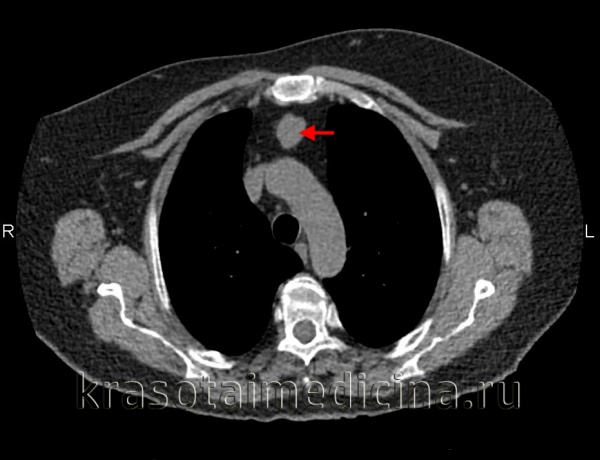

(а) У этого же пациента при КТ с контрастным усилением в средостении определяется объемное образование жировой плотности с криволинейными толстыми мягкотканными перегородками и узелками. При наличии перегородок толщиной более 2 мм и мягкотканных узелков следует заподозрить скорее липосаркому, а не липому.

(б) У этого же пациента при КТ с контрастным усилением на реконструкции в коронарной плоскости визуализируются распространение липосаркомы в заглоточное пространство и циркулярный охват дуги аорты и крупных сосудов.